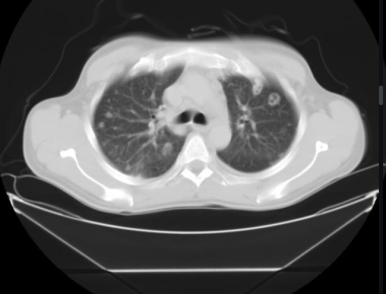

§ Multiple cavitary lesions / nodules (다발 공동성 결절)

- 다발 공동성 병변은 주로 혈관계 전파로 인해 발생한다

- Septic emboli

- Vasculitis : ex) Wegener granulomatosis

- Metastasis :ex) SCC, uterine carcionsarcoma